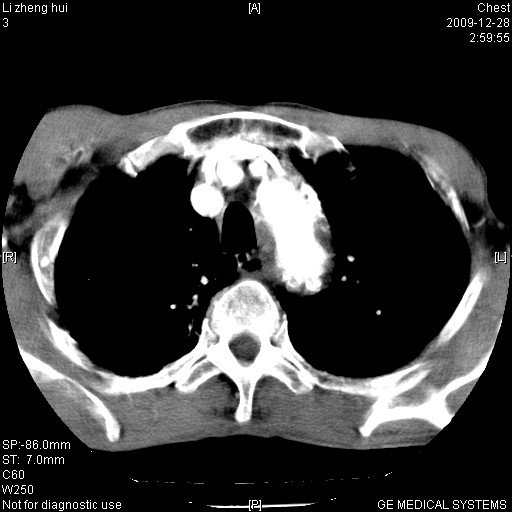

标题: CT23859:胸主动脉瘤

男  79岁 胸部痛急诊入院,晚上做的增强

考虑主动脉瘤?(增粗、钙化、壁血栓?)

支持降主动脉瘤,不考虑夹层

动脉瘤伴附壁血栓

1)考虑胸主动脉壁间血肿或夹层动脉瘤。2)多发性肝囊肿。

1)考虑胸主动脉附壁血栓或夹层动脉瘤。2)多发性肝囊肿。

考虑大动脉炎,附壁血栓形成。